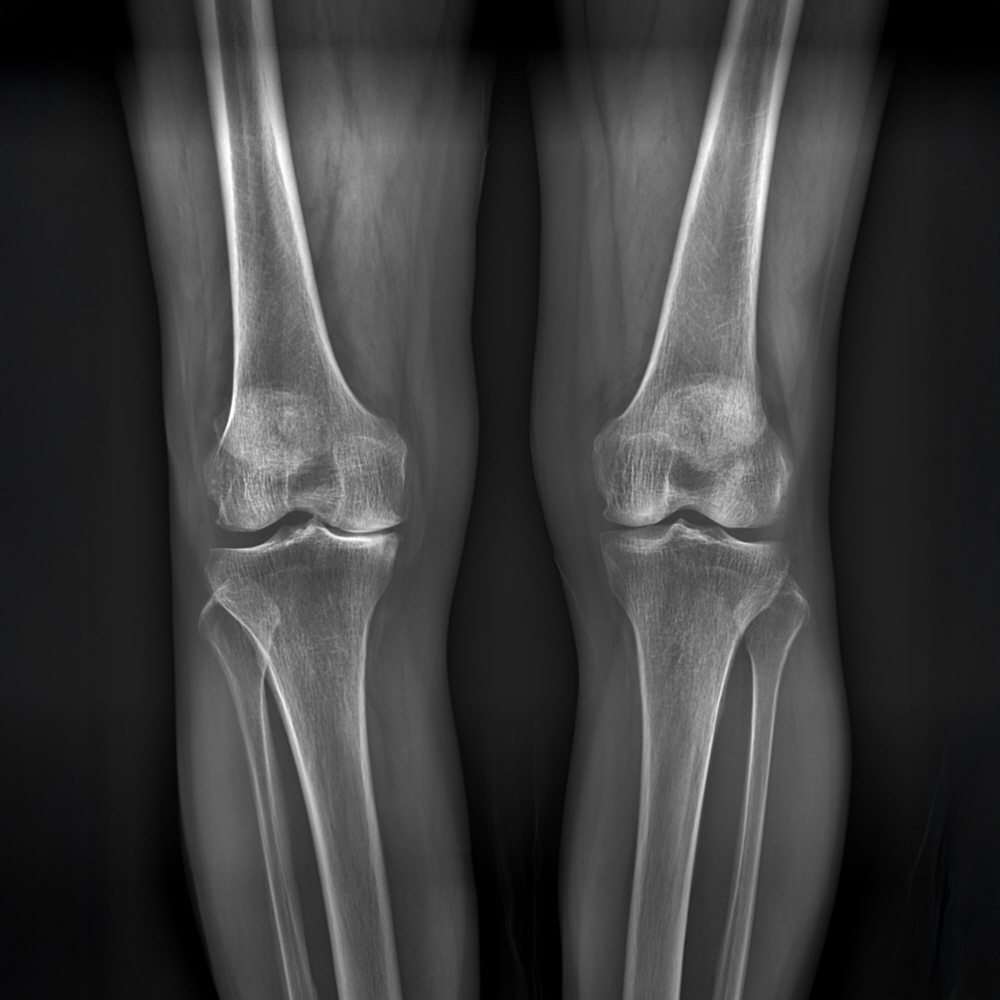

(KL Grade 1)

(KL Grade 2)

(KL Grade 3)

(KL Grade 4)

무릎 엑스레이 검사를 통해 관절염의 진행단계를 평가하는 방법으로 초기, 중기, 후기, 말기의 4단계로 나누어 진단하는 방법으로 방사선 사진 상 관절부위의 이상골격(관절간격 유지여부, 골극 형성, 연골하 경화소견 등)을 나타내는 평가지표이며, Grade III이상은 중등도 이상의 손상이 있음을 의미합니다.

KL Grade 1

임상적으로 의심스러운 퇴행성관절염 및 미미한 골 증식이 보임

KL Grade 2

경도 퇴행성관절염. 관절간격이 유지는 되나 골극이 형성되는 단계

KL Grade 3

중증도 퇴행성관절염, 골 증식이 grade2 에 비해 뚜렷하며 골극형성뿐 아니라 연골 마모에 의해 관절간격도 좁아지게 되는 단계

KL Grade 4

심각한 퇴행성관절염으로 연골이 거의 다 닳아 관절간격이 소실되어 뼈끼리 맞닿게 되고 연골하 경화 및 다량의 골극형성이 되는 마지막 단계